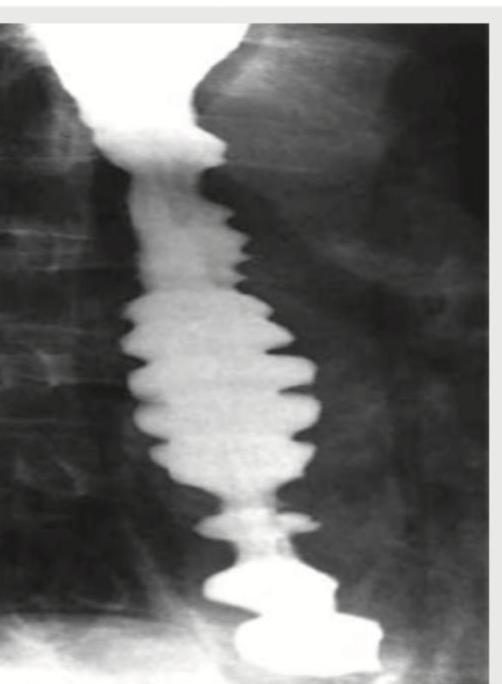

A patient complains of episodes of dysphagia and chest pain. The barium study presentation of the patient is shown below. A radiologist will describe this condition as all except:

Explanation: ***Diffuse esophageal spasm*** - The image shows a **"corkscrew" or "rosary bead" esophagus**, which is a classic radiographic finding in diffuse esophageal spasm due to uncoordinated esophageal contractions. - Dysphagia in this context, coupled with a normal UGI endoscopy (ruling out mechanical obstruction visible by scope), points to a motility disorder. *Zenker's diverticulum* - This is an **outpouching of the pharyngeal mucosa** occurring above the upper esophageal sphincter. - It would typically appear as a distinct barium-filled pouch on a barium swallow, not the diffuse spasm seen in the image. *Dysphagia lusoria* - This is dysphagia caused by **vascular compression of the esophagus**, usually an aberrant right subclavian artery. - It would manifest as a localized external compression rather than the widespread functional spasm shown. *Esophageal carcinoma* - Esophageal carcinoma would typically present as a **fixed filling defect, stricture, or ulceration** on a barium swallow, often with abnormal mucosal patterns. - The UGI endoscopy would likely show an abnormality if carcinoma were present.

Explanation: ***Cobble stone appearance*** - **Cobblestone appearance** on barium swallow studies is typically associated with **Crohn's disease** affecting the bowel, characterized by deep ulcerations intersected by edematous mucosa. - This image clearly shows severe, disorganized contractions in the esophagus, which is characteristic of a **motility disorder**, not Crohn's. *Corkscrew appearance* - The image distinctly shows a **twisted, irregular contour** of the esophageal lumen, which is well-described as a **corkscrew esophagus**. - This finding is classic for **diffuse esophageal spasm** (DES), where powerful, uncoordinated contractions occur. *Rosary bead esophagus* - This term is another descriptive phrase for the appearance of the esophagus in **diffuse esophageal spasm**. - The appearance resembles beads on a rosary due to the **simultaneous, non-peristaltic contractions** causing segmental narrowing and outpouching. *Pseudodiverticula* - While not true diverticula which are herniations of all layers, the saccular outpouchings seen between the spastic contractions can be described as **pseudodiverticula**. - These are formed by the irregular, forceful contractions transiently distorting the esophageal wall.